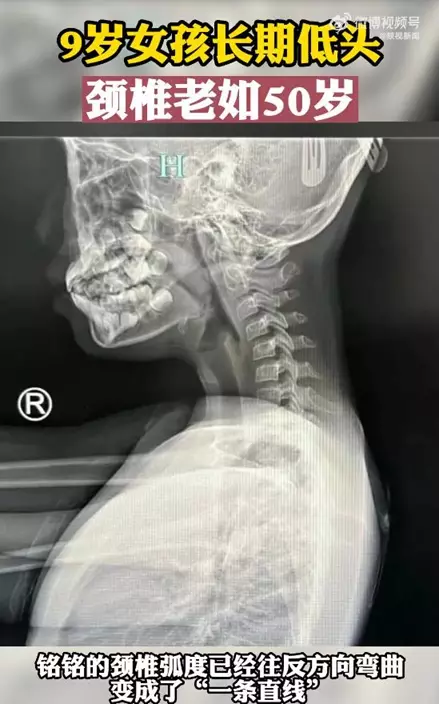

浙江杭州一名9歲女孩銘銘最近常出現脖子酸痛、手指發麻等症狀。醫生檢查後發現她的頸椎已老化如50歲長者,人的正常頸椎是呈正「C」形,而女童的頸椎弧度往反方向彎曲變成「一條直線」。原來,銘銘除了平時寫功課外,還沉迷於玩手機,經常一玩就是幾個小時,因此導致了嚴重的脊椎病,醫生藉此提醒各位家長,一定要關注子女的脊椎健康問題。